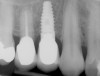

Figure 4  Radiograph of the implant restoration in the maxillary left lateral incisor shown in Figure 3.

Figure 4